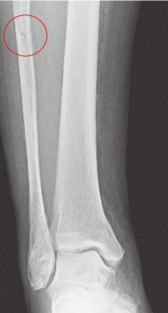

脛骨遠位骨端線損傷

脛骨遠位骨端線が閉鎖する時期に限定されます。Triplane 骨折は12~15 歳頃に好発する骨折で、脛骨の骨端線の閉鎖時期と閉鎖の仕方に関係しているとされています。

(図18) Triplane 骨折 左 レントゲン 右CT画像

(図18)MB Orthop. 38(5):55—64,2025大人とこどものスポーツ外来 下肢編【こども編】小児アスリートの足関節・足部捻挫に対する外来診療 田中 博史より抜粋

(図19)整形外科Surgical Technique vol.12 no.5 2022 52‐57(604‐609)[手術法] こどもの足関節周囲骨折・ Juvenile Tillaux・Triplane骨折 依光正則 より抜粋一部変更

Triplane 骨折は、Salter-Harris分類ではⅣ型にあてはまります。Ⅲ型は、Tillaux骨折といいます。脛骨遠位端骨折はⅠ/Ⅱ型が50%、Ⅲ型が25%、Ⅳ型が10%の頻度で発生するとされています。手術適応はⅡ~Vで考慮されます。Ⅴは骨端線がつぶれた状態です。